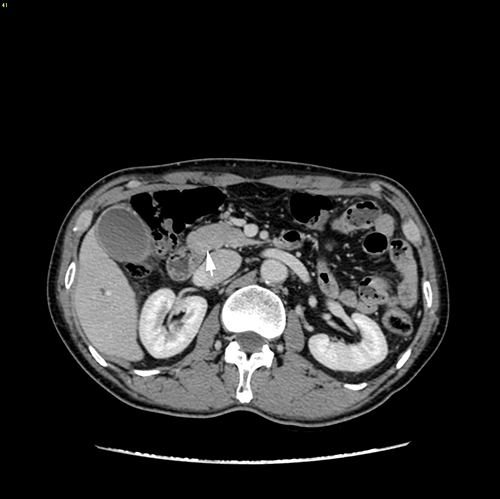

胆总管下端癌--胰十二指肠切除